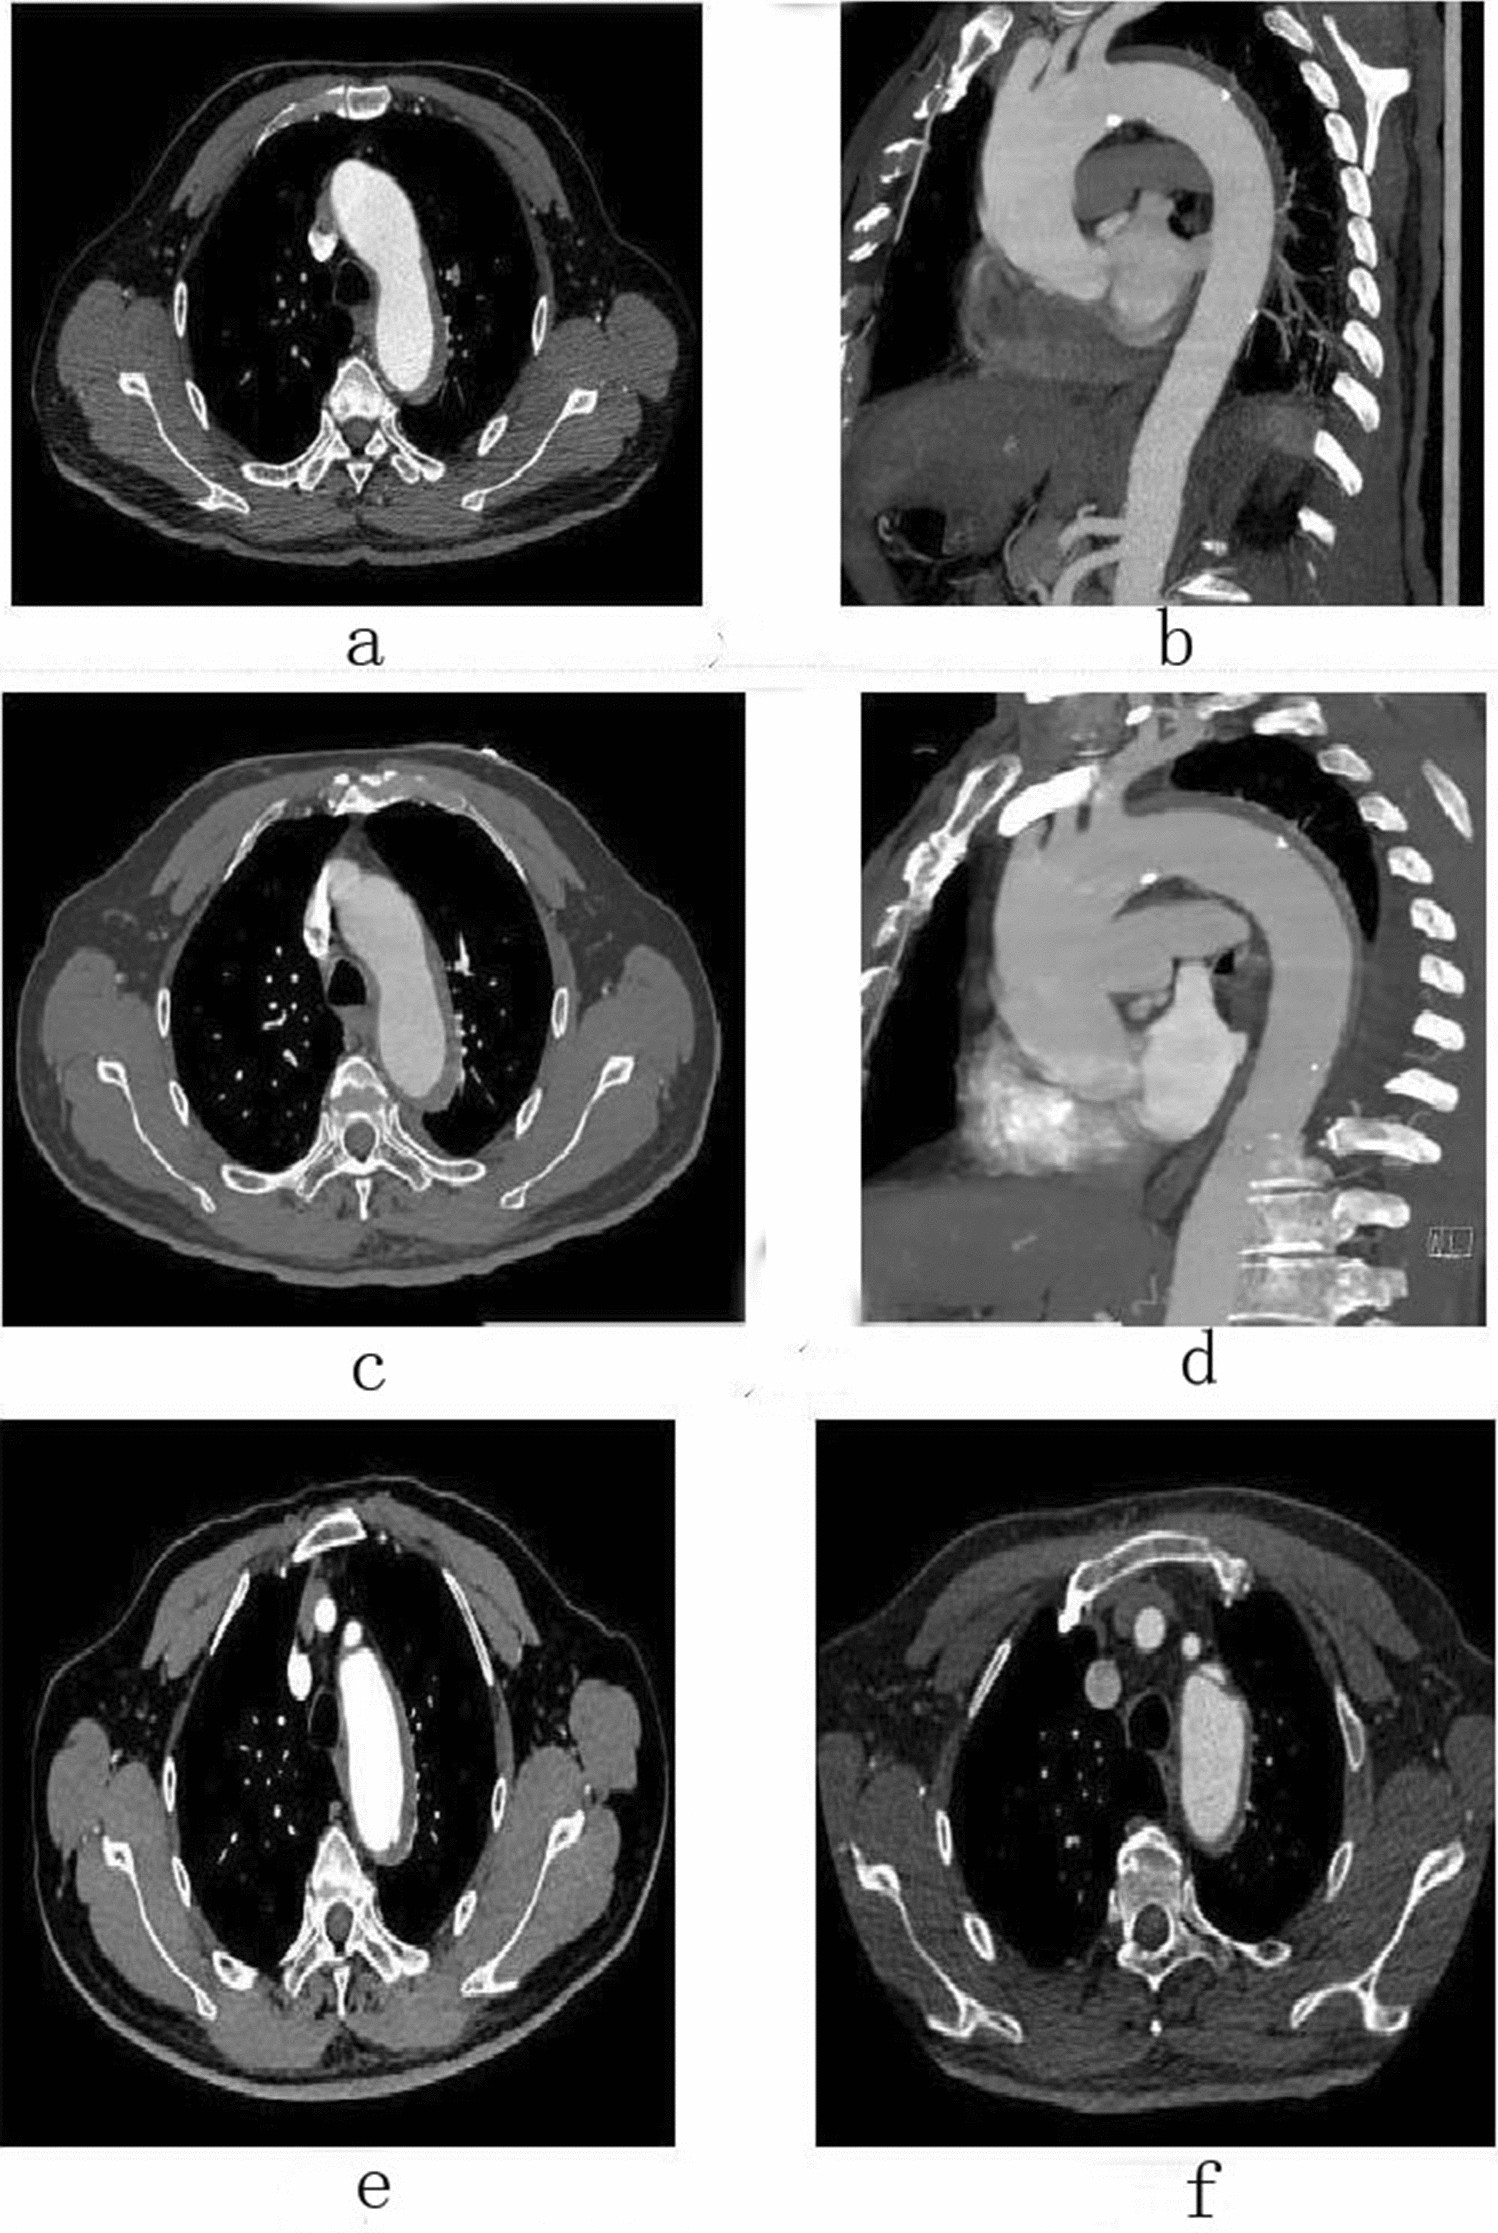

Figure 4

Male, 67 years old, admitted to hospital for “sudden pain in chest for 9 h”, Diagnosis: Stanford type B aortic dissection; Treatment: IMH conservative treatment. CTA of the patient in different periods: (a) Admission; (b) Admission; (c) 3 days after admission; (d) 3 days after admission; (e) 3 months after admission; (f) 11 months after admission.